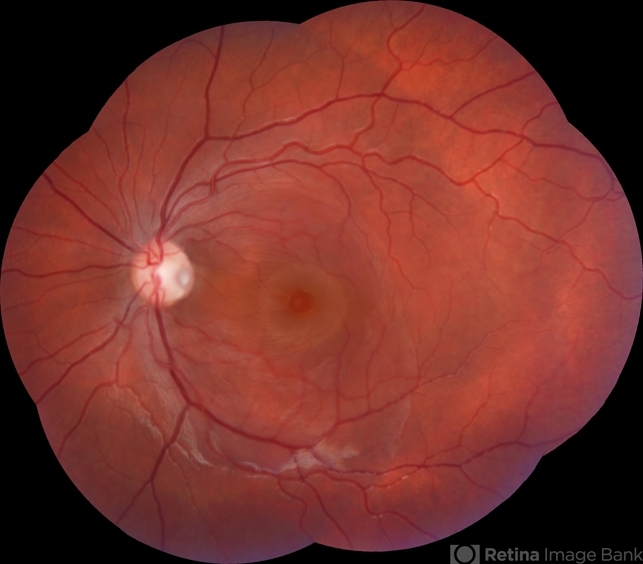

- Montage fundus photograph of 13 years old female patient with optic pit and associated maculopathy in left eye